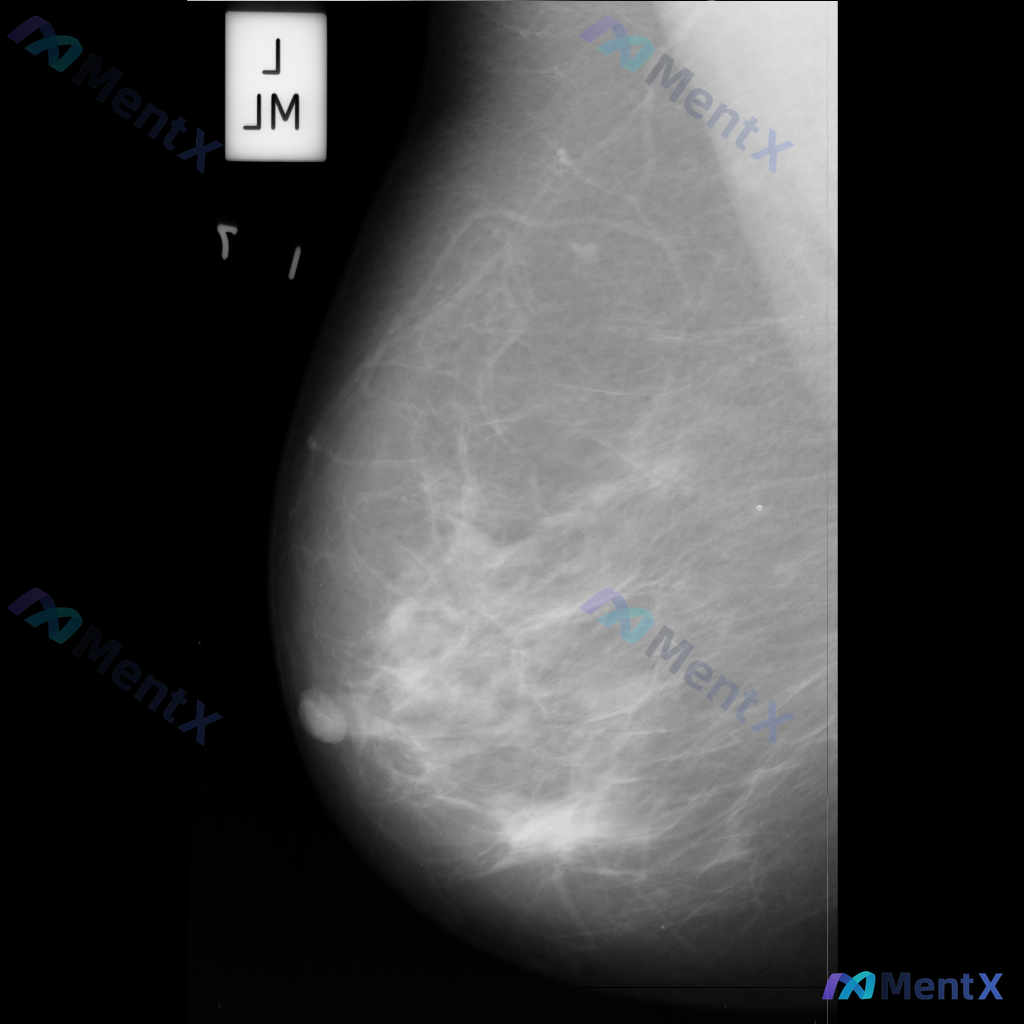

整理到一份单张乳腺钼靶影像的资料,分享给大家讨论: - 背景:乳腺整体为多量腺体型或致密型(BI-RADS C/D型可能) - 主要异常:在乳腺中下部略偏中央区域,可见局灶性不对称密度,或伴有轻度腺体结构紊乱 - 伴随征象:未见明确簇状/线样等可疑恶性钙化,无明确结构扭曲、皮肤增厚/回缩、乳头内陷等...

整理到一张乳腺钼靶影像的讨论资料,先把关键信息列出来,大家帮忙看看: - 影像类型:左乳内外斜位(MLO位)钼靶 - 背景:乳腺呈多量腺体型(致密型),腺体组织丰富 - 主要发现:左乳下象限可见局灶性不对称密度,伴有腺体结构轻度紊乱 - 其他:目前未见明确的异常钙化、导管增粗或皮肤异常 单看这张影像...